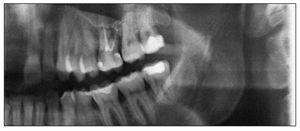

Figura 4. Detalle de una radiografía panorámica con el diente 26 de tres raíces endodonciado.

Figura 5. Reproducción por separado de los conductos obturados de las raíces palatina, mesial y distal.